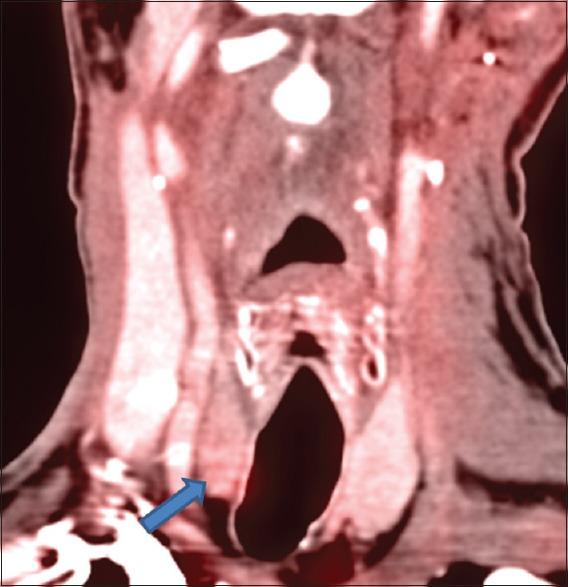

Metastasis to the thyroid gland is rare; furthermore, intrathyroid metastasis from head and neck squamous cell carcinoma (SCC) is very unusual, with only nine previously documented cases four from intrathyroid metastasis from nasopharyngeal carcinoma, two from oral cavity, one each from oropharynx, larynx, and parotid. The reported case series are unique in nature and illustrates the role of fluorodeoxyglucose positron emission tomography-computed tomography (PET-CT) and ultrasound-guided biopsy in diagnosing clinically occult isolated intrathyroidal metastasis, which helps in the best management for an isolated intrathyroid metastases. This study details the cases of three patients who were diagnosed with intrathyroidal metastasis from SCC of the tongue by PET-CT, followed by USG-guided biopsy, who were treated with either surgery and or chemotherapy. Although intrathyroidal metastasis is an uncommon occurrence and signifies poor prognosis, early detection of an isolated intrathyroidal metastasis on imaging in an appropriately selected patients, radical surgery, and/or chemotherapy improve local control and quality of patient's life.

甲状腺转移瘤较为罕见;此外,头颈部鳞状细胞癌(SCC)发生甲状腺内转移的情况非常少见,此前仅有9例记录在案的病例——4例来自鼻咽癌的甲状腺内转移,2例来自口腔,1例分别来自口咽、喉和腮腺。所报道的病例系列具有独特性,说明了氟脱氧葡萄糖正电子发射断层扫描-计算机断层扫描(PET-CT)和超声引导下活检在诊断临床隐匿性孤立性甲状腺内转移瘤中的作用,这有助于对孤立性甲状腺内转移瘤进行最佳管理。本研究详细介绍了3例经PET-CT诊断为舌部SCC甲状腺内转移、随后接受超声引导下活检、并接受手术和/或化疗的患者病例。虽然甲状腺内转移并不常见且预示预后不良,但在适当选择的患者中通过影像学早期发现孤立性甲状腺内转移瘤、进行根治性手术和/或化疗可改善局部控制并提高患者生活质量。